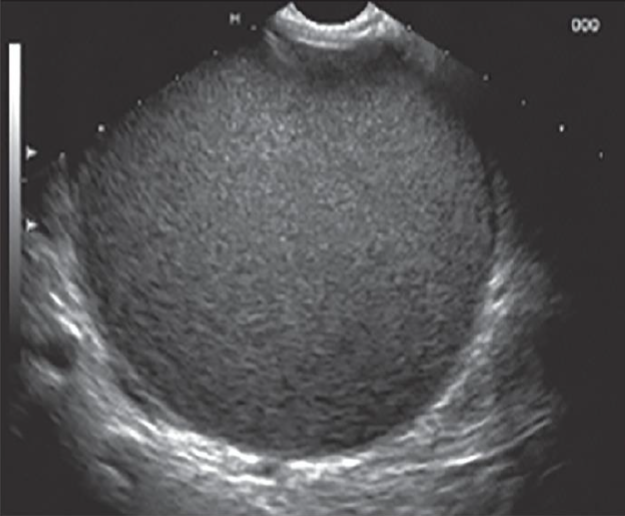

מהו הממצא

A

פסאודו-סיצטה, ציסטה שאינה צלולה

**נראה בד”כ אחרי טראומה או דלקת לבלב